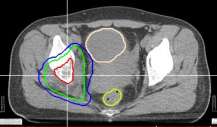

患者赵xx,女,42岁,MR:右侧髋臼窝及坐骨内异常信号,邻近肌肉及股骨小转子区域不同程度受侵。CT:右肺下叶见片状高密度影,气管及主支气管开口通畅,纵隔见结节状软组织影,较大者短径为13mm。右侧坐骨及右侧髋臼密度减低,形态欠规整。临床诊断:右肺下叶腺癌(cT2N2M1 Ⅳ期),纵隔淋巴结转移,多发骨转移。患者腰骶部疼痛明显,疼痛致活动受限,轮椅推入病房。2016年6月给予姑息减症放疗,靶区包括右侧骨盆转移灶(右股骨上段、右坐骨、右耻骨、右髂骨后段),6MV-X线调强放疗,单次量4Gy,放疗组织剂量24Gy/6次/8天。放疗后患者疼痛缓解,现行动自如。